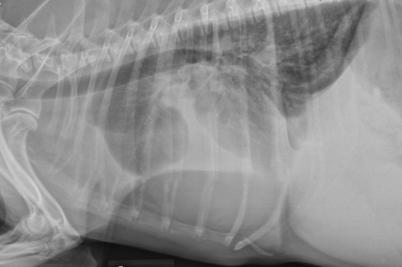

Radiographic changes associated with pleural effusion include increased soft tissue density in the ventral chest with rounded lung lobe margins and obscuration of the normal cardiac silhouette. Widened interlobar fissure lines are consistent with pleural fluid accumulation.

In this radiograph the lung lobes are displaced dorsally and there is a diffuse interstitial to alveolar pattern, likely as a result of atelectasis secondary to fluid accumulation in the space lungs normally occupy.

Image courtesy of Dr. Teri Defrancesco.